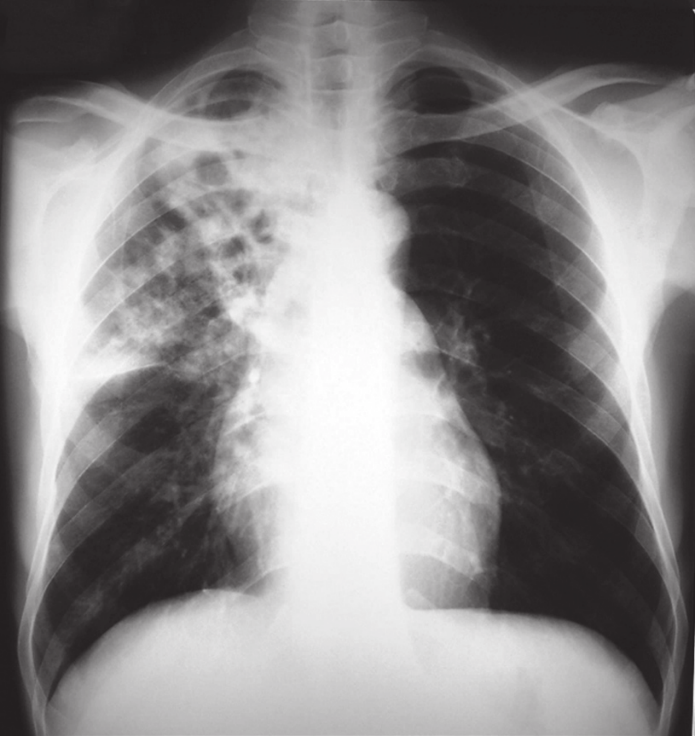

5.1 Chest Radiography (CXR)

The chest X-ray is the primary screening tool.

• Primary TB: Often presents with hilar lymphadenopathy and lower lobe infiltrates (Ghon complex).

• Post-Primary (Reactivation) TB: Classically involves the upper lobes (apical or posterior segments). The hallmark finding is cavitation—a thick-walled hollow space formed by caseous necrosis. This is highly suggestive of infectiousness [2].

Figure 4. Anteroposterior (AP) chest radiograph of a patient with advanced pulmonary tuberculosis. The image reveals a large cavity in the right apical region (upper lung field), indicated by the arrow. This finding is characteristic of post-primary (reactivation) TB and indicates high infectivity.

(Source: Centers for Disease Control and Prevention (CDC), Public Health Image Library (PHIL), ID #14805, 1972).